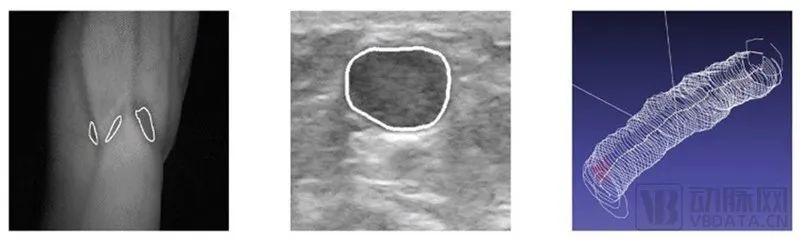

NIR(近红外光)的穿透深度有限,对于肥胖患者不能准确使用,因此Vitestro对患者静脉采用了NIR+超声波的组合技术作为设备的“眼睛”,进行血管的识别。识别的同时AI算法持续跟进,将采血机器人“看”到的血管信息通过3D技术重建为图像。并且保持整个过程所追踪到的全部信息和数据都随患者静脉的变化实时更新。

图1:近红外线检测静脉 图2:用Al在超声波中追踪静脉 图3:实时创建静脉的3D图像

图源:Vitestro官网